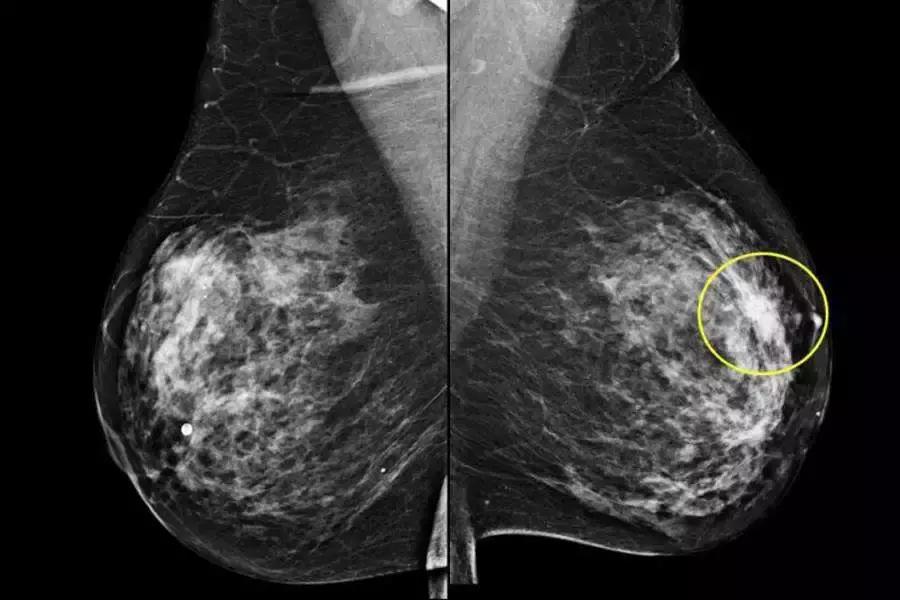

辅助检查是进一步明确诊断的手段,主要包括彩色超声检查,乳腺X线钼靶摄片和选择性乳腺导管造影X线检查,对有乳头溢液者还可选择进行纤维乳管镜检查。

对可疑病灶进行病理学穿刺活检排除乳腺癌。对乳腺增生症病理形态学诊断仍然是临床诊断的金标准。

需要指出的是,针对40岁以上的女性患者,特别是有乳房局限性增厚或肿块样改变者,不能轻易诊断为乳腺增生症,需要进行上述检查排除乳腺癌之后方可诊断为乳腺增生症。